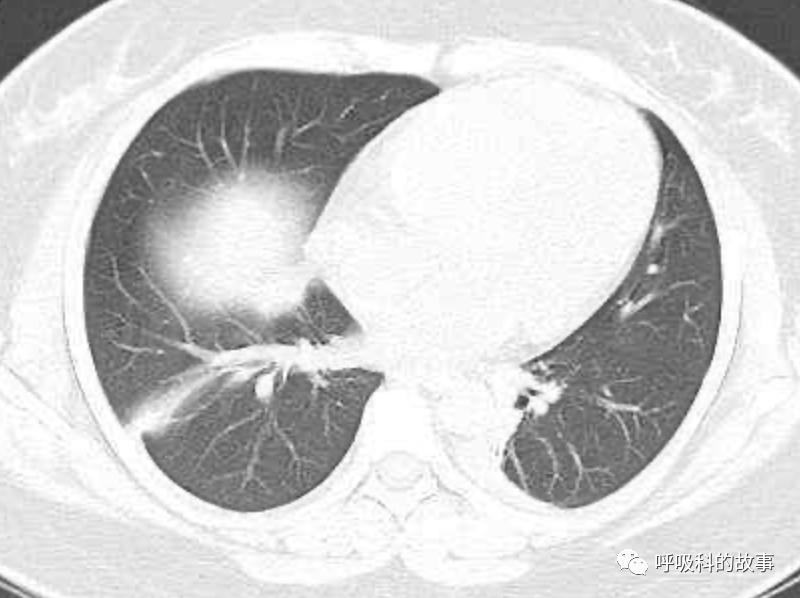

患者发热后行胸部CT检查(6月21日,住院第13天),可见两下肺有条片影,当时斟酌是肺炎引起的发热。

可是在6月26日(往院第18天)仍持续发热的情况下复查肺部CT,肺部病灶已明显吸收了。那么患者发热的原因到底是什么呢?为什么患者高热的情况下血白细胞不升反降,C反应蛋白也没有明显增高?这个时候消化科医生也迷茫了,这可怎么办?于是请感染科和呼吸科医生一起会诊,共商计策。